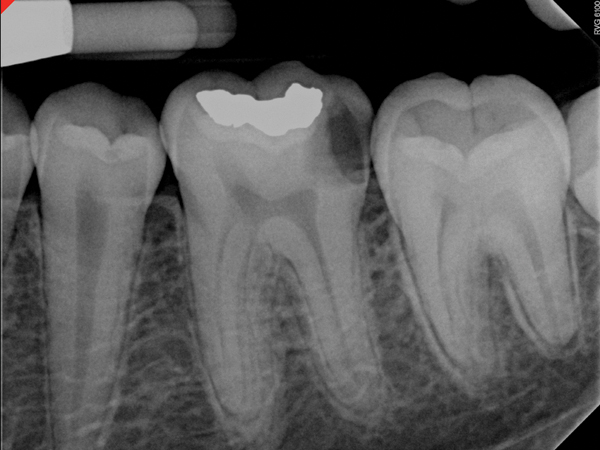

Figure 11. Preoperative radiograph. Courtesy of Dr. Guillaume Jouanny.

Figure 11

Figure 12. Postoperative radiography after full pulpotomy was performed. Courtesy of Dr. Guillaume Jouanny.

Figure 12

Figure 13. Tooth was asymptomatic at 1-year follow-up. Courtesy of Dr. Guillaume Jouanny.

Figure 13

Figure 14. Contralateral tooth at 1-year follow-up. Courtesy of Dr. Guillaume Jouanny.

Figure 14